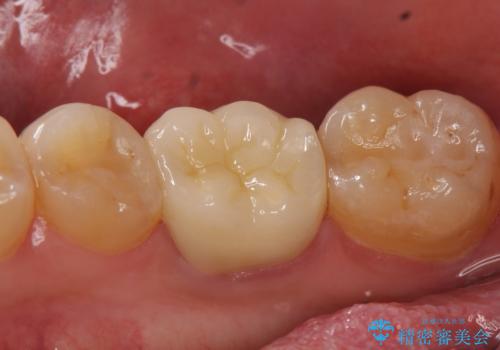

その後症状の消失を確認し、オールセラミッククラウンによる補綴を行いました。

今回用いたオールセラミッククラウンはジルコニアフレームという白い素材の上にセラミックを盛っているため、審美性が非常に高いのが特徴です。

また、ジルコニアは人工ダイヤモンドの材料にも使われているほど高い強度を持っており、そのためオールセラミッククラウンは審美性だけでなく、奥歯やブリッジの補綴も可能とするクラウンです。